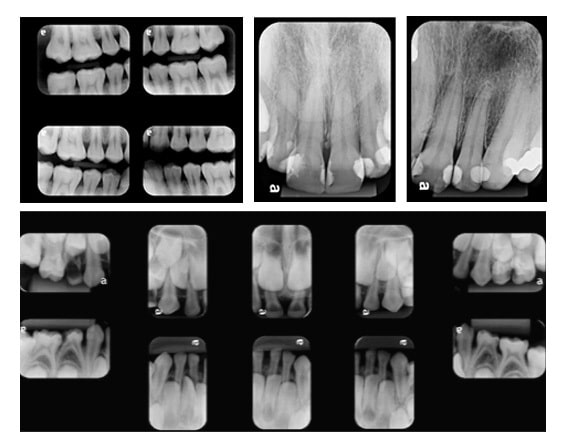

PERIAPICAL

Abrange o dente em toda a sua extensão: coroa, raiz e tecidos de sustentação. É dividida em regiões específicas da boca, com imagens detalhadas dos incisivos centrais, caninos, incisivos laterais, molares e pré-molares.

INTERPROXIMAL

Também conhecida como Bite-Wing, ela visualiza as coroas dos dentes molares e pré-molares (superiores e inferiores) no mesmo filme, com precisão, para o diagnóstico de lesões de cárie, cristas marginais, pontos de contato e presença de tártaro.